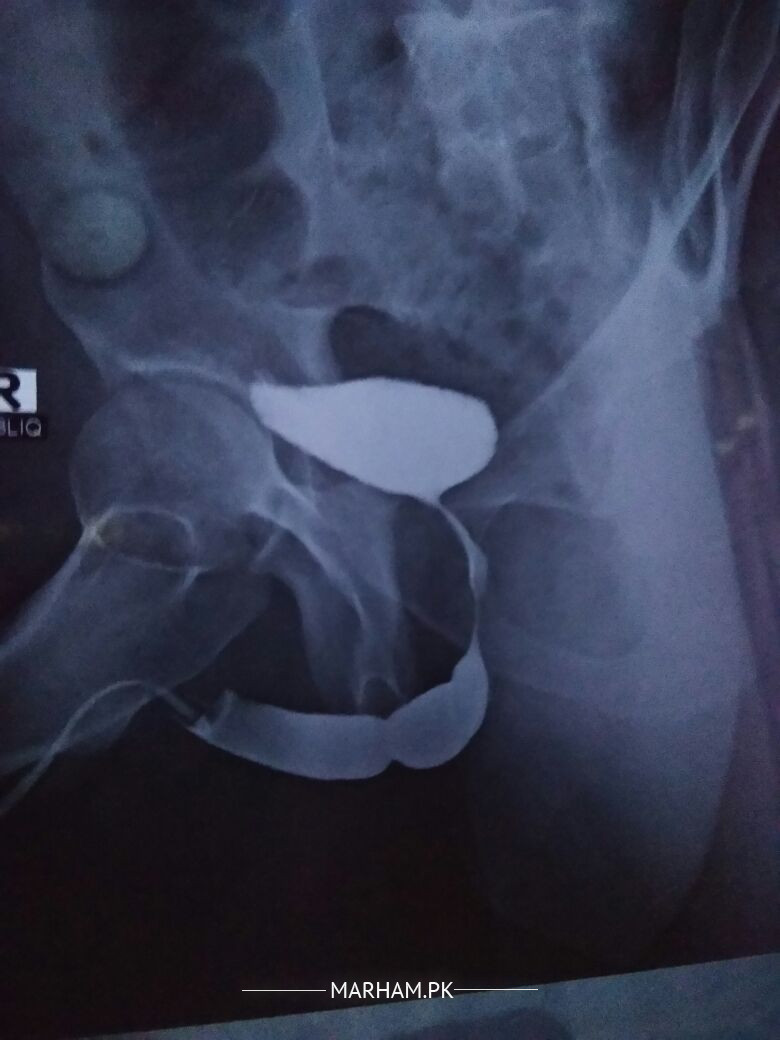

is there any urethral stricture in my Urethragram X Ray, as attached, my avg Urine flow rate is 5.6 ml/sec

yes it seems to b a partial structure in this film. however need detail history, examination nd more films to confirm

May be